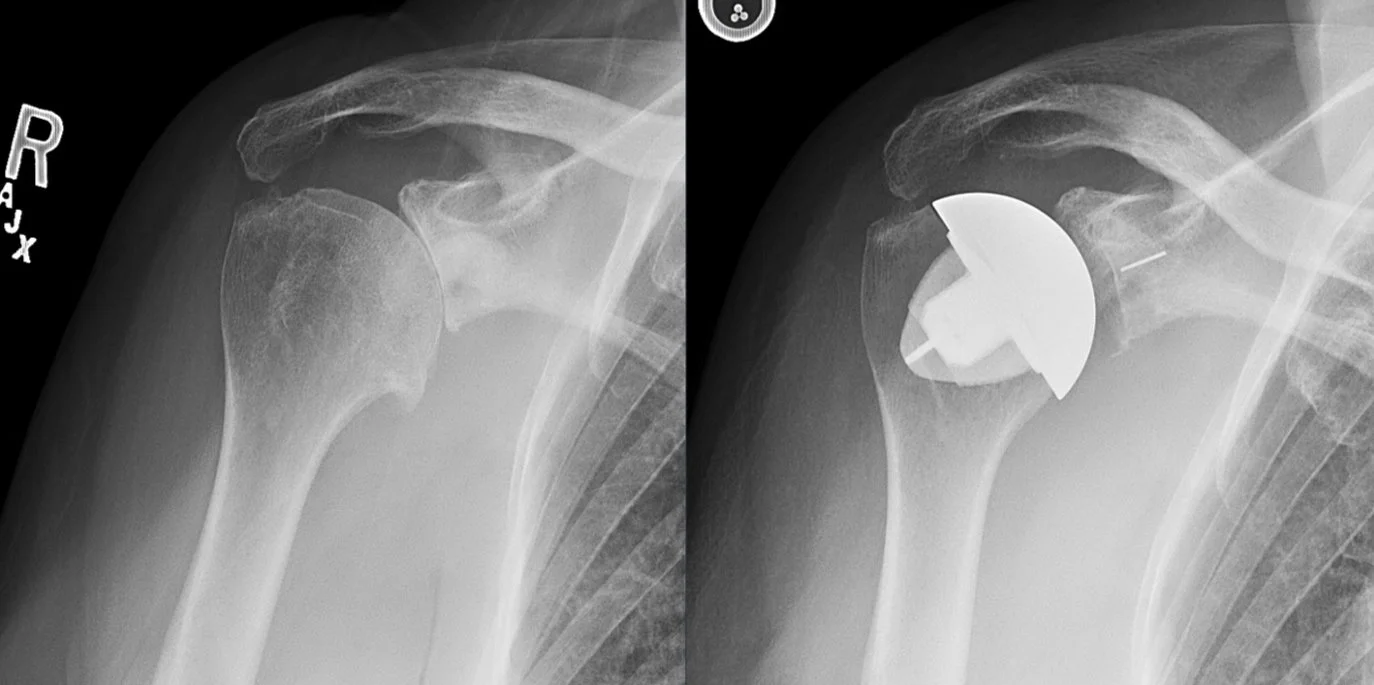

As the process of arthritis progresses, continued loss of cartilage will lead to narrowing and eventual complete loss of joint space as seen on X-ray. This is sometimes referred to as “bone-on-bone” arthritis. With continued cartilage degradation, there is no longer a smooth frictionless surface with shoulder motion and activity. As you can imagine, as joint surfaces become fissured and roughened due to arthritis, like grinding two pieces of sandpaper against one another, continuing shoulder activity and motion leads to inflammation of the joint.

Ultimately, the definitive treatment for end-stage shoulder arthritis is total shoulder arthroplasty (replacement). This involves replacing the arthritic humeral head (ball) with a metal implant, and the glenoid (socket) with a highly cross-linked polyethylene plastic liner.

This type of shoulder replacement is called anatomic total shoulder replacement, because the native humeral head (ball) is replaced by an implant with a spherical surface, and the native glenoid (socket) is replaced with an artificial socket. Optimal outcomes after anatomic total shoulder replacement requires a well-functioning rotator cuff, which will be confirmed by Dr. Koscso pre-operatively based on physical examination and/or imaging.